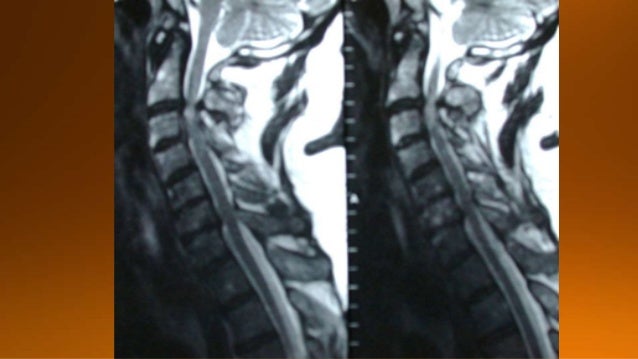

17. 17. NMO presenting with neuritis optica (arrows).The brain is normal